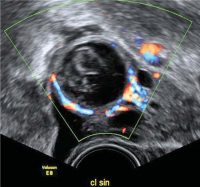

Tipps und Tricks im Gyn-Ultraschall: Sonographische Kennzeichen des Corpus luteum

Journal für Gynäkologische Endokrinologie 2013; 7 (4) (Ausgabe für Österreich): 24-26 Journal für Gynäkologische Endokrinologie 2013; 7 (4) (Ausgabe für Schweiz): 28-30 Volltext (PDF) Abbildungen